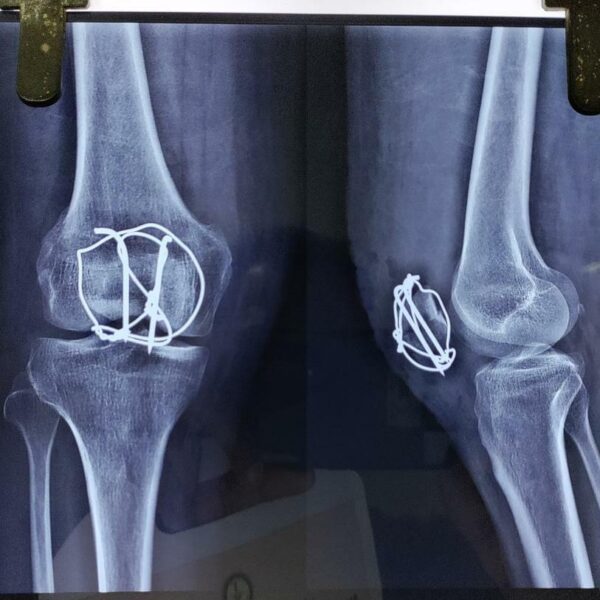

Moments That Mark Meaningful Recovery

Witness real patient transformations at The Ortho Clinic through images that reflect successful treatments and restored mobility.